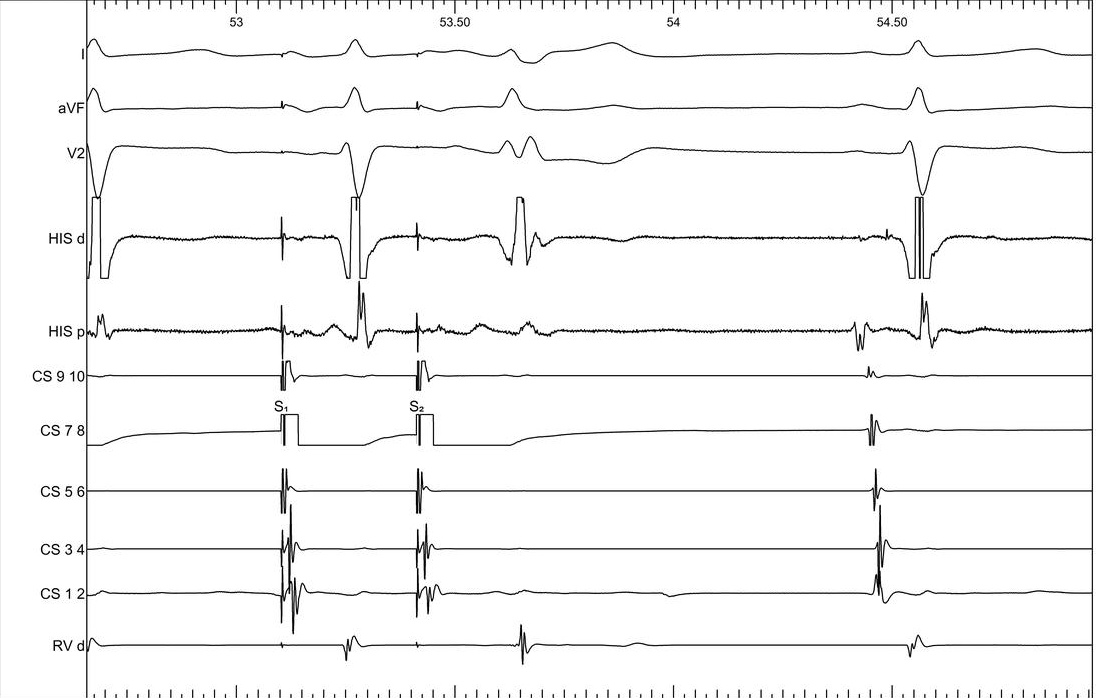

Single ventricular extrastimulus

02_rv_600_300.jpg